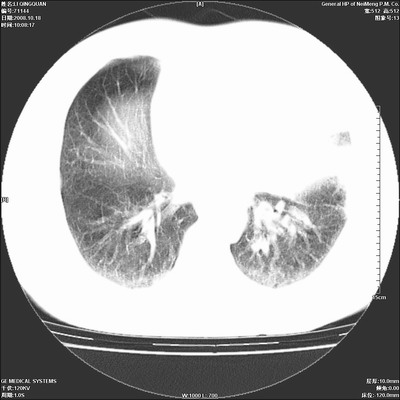

以下是引用duguo在2008-10-19 13:59:00的发言:[br]左肺上叶支气管狭窄,首先考虑中心型肺癌伴阻塞性肺炎\\肺不张.

以下是引用ybing在2008-10-19 12:58:00的发言:[br]左肺上叶阻塞性炎症-建议支气管镜进一步检查除外中央型肺癌

以下是引用随光逐影在2008-10-19 14:31:00的发言:[br]考虑左肺中央型肺癌并左肺上叶阻塞性肺炎,肺不张。